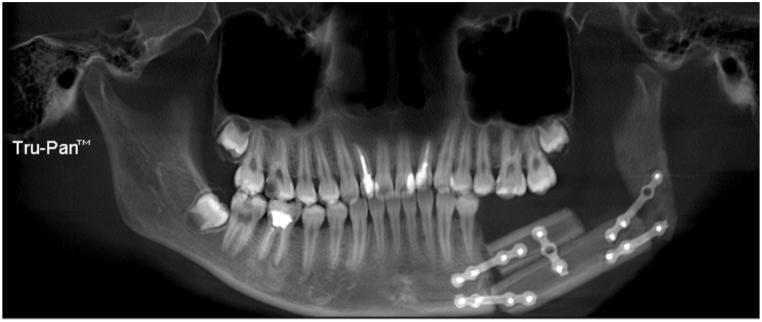

We reviewed patients who underwent mandibular reconstruction with FFF from 2015 to 2021 and classified the mandibular defects into five categories: classⅠ(unilateral-mandibular excluding condyle), classⅡ(unilateral-mandibular including condyle), classⅢ(bilateral-mandibular excluding condyle), classⅣ(bilateral-mandibular including one condyle), and classⅤ(bilateral-mandibular including both condyles). Cone Beam Computed Tomography (CBCT) data were collected preoperatively(T0), at 7-10 postoperative days(T1), 6 postoperative months(T2), and 1 postoperative year(T3). We calculated the condylar surface area, volume, and displacement.

62 cases were collected. The condylar surface areas and volumes in T2 and T3 values were lower than those of T0 and T1(P < 0.01) The condylar displacement was the lowest in ClassI and the largest in ClassⅣ(P < 0.01), while no significant differences in classesⅠ-Ⅲ(P < 0.05). Displacement during T1-T0 was greater than that during T2-T0 and T3-T0(P < 0.05).

Mandibular reconstruction with FFF results in displacement and alteration of the condyle within a time interval, and this alteration stabilizes after 6 months. Mandibular defects that do not reach the midline, surgical alteration to preserve the condyle are not required. However, when the defects cross the midline, the condyle should be preserved as much as possible.